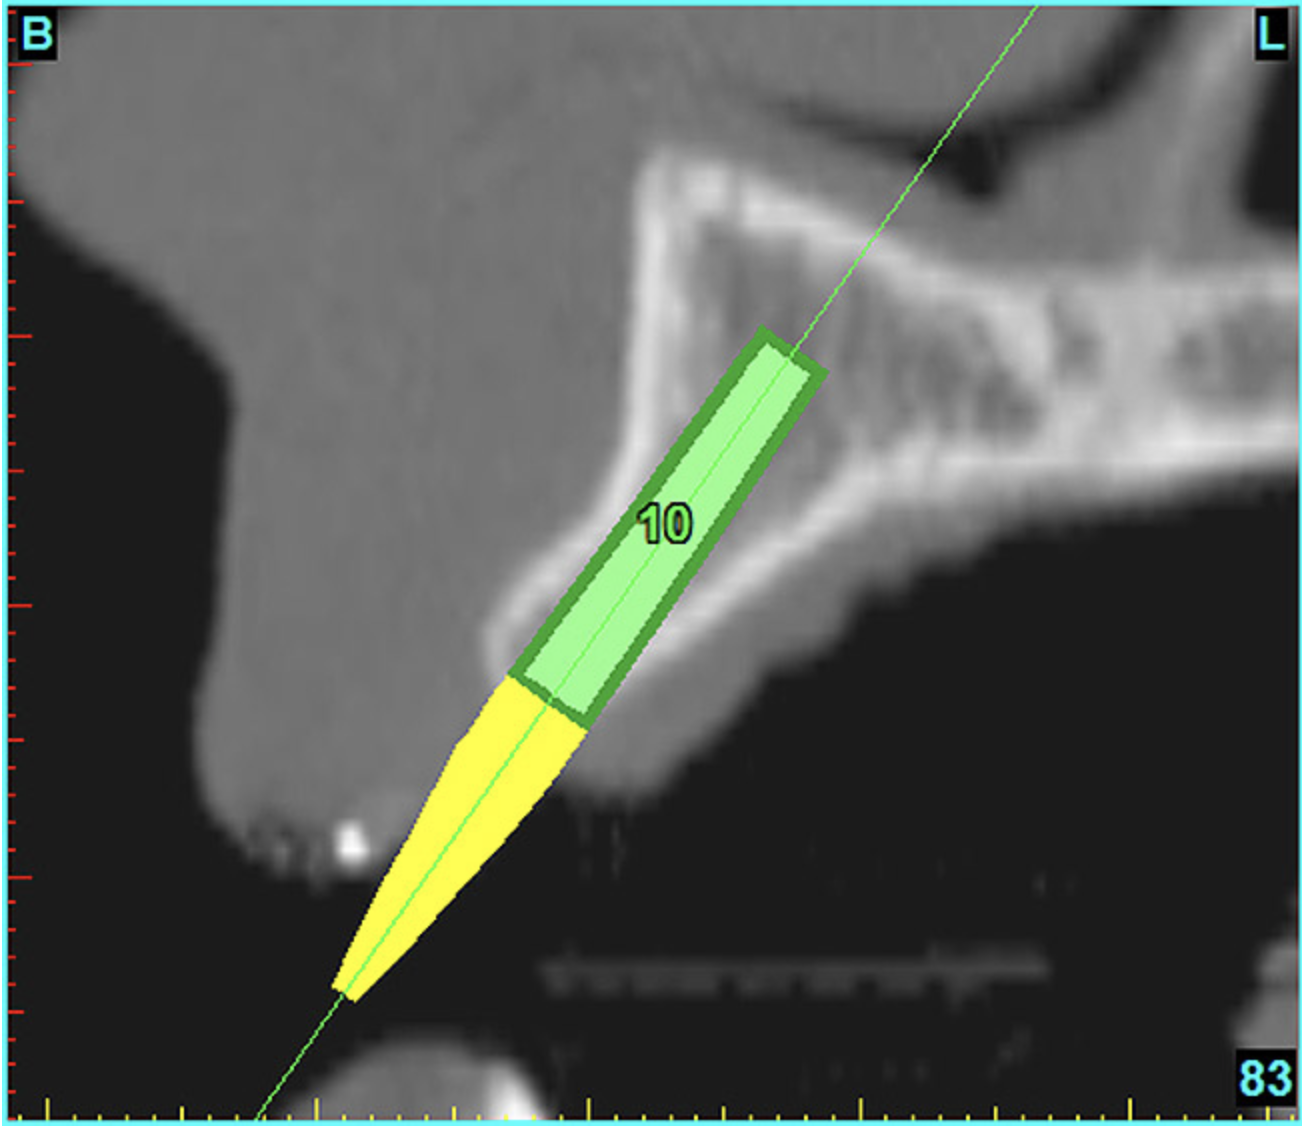

Using the interactive treatment-planning software application, the scan data was assimilated and both potential lateral incisor implant receptor sites were evaluated. It is a combination of the data and the methodology used to interpret the data that is the basis for defining a new paradigm in diagnosis and treatment planning. Proper evaluation of these images and correct use of the interactive treatment-planning software tools is essential in creating a decision tree of treatment options. First, the data from the scan was reformatted into panoramic, axial, and cross-sectional images. The undistorted cross-sectional images revealed the residual alveolar bone in the area of the right lateral incisor. Then, a simulated schematic implant was placed within the bone with an abutment extension to help visualize the connection to the restorative position of the tooth (Figure 4A). The Triangle of Bone® (TOB), a concept developed by the author to analyze bone quality, quantity, and disposition at prospective dental implant sites using CBCT scans, aided in determining available bone volume by defining a “zone” for proper implant placement18,19 (Figure 4B).

After reviewing the CT data and the decision tree, the bone within the “zone” of the TOB was evaluated and found to be satisfactory for implant placement. Because the goal of implant dentistry is not the implant but the tooth that is placed, true restorative-driven implant dentistry must begin with the assumption that the implant position should remain consistent with the tooth it is replacing, and the final implant-supported restoration.12,22-26 The TOB aids the clinician in understanding the link between the implant position and the desired restorative goal. The base of the geometric shaped “zone” is visualized by starting at the widest area of alveolar bone facially and superiorly. The apex of the triangle is positioned to bisect the alveolar crest (Figure 4B). The TOB, the overlay in the cross-sectional image, reveals whether adequate bone is available for implant placement. It also helps to identify concave facial bone defects, and accurately determine the width of bone at the crest. The author recommends using an interactive software application that provides the necessary measurement tools to accurately assess the bone anatomy.

By using interactive treatment-planning software, the author was able to assess implant-to-tooth distances based on actual undistorted measurement of distances at both the crest (Figure 11A) and the apex (Figure 11B) of the implant. Additionally, the ability to section the 3D model allowed extremely accurate virtual implant placement, ensuring 2 mm of facial and palatal bone surrounding the implant (Figure 12A). Using advanced masking tools, further manipulation of the 3D maxilla provided an unparalleled appreciation not only of the potential implant receptor sites, but also of the alveolar complex of each existing tooth and root morphology (Figure 12B).

Figure 11a  By zooming in on the digital image, the implant-to-tooth distances can be assessed at the (A) crest and the (B) apex.

Figure 11a

Figure 11b  By zooming in on the digital image, the implant-to-tooth distances can be assessed at the (A) crest and the (B) apex.

Figure 11b